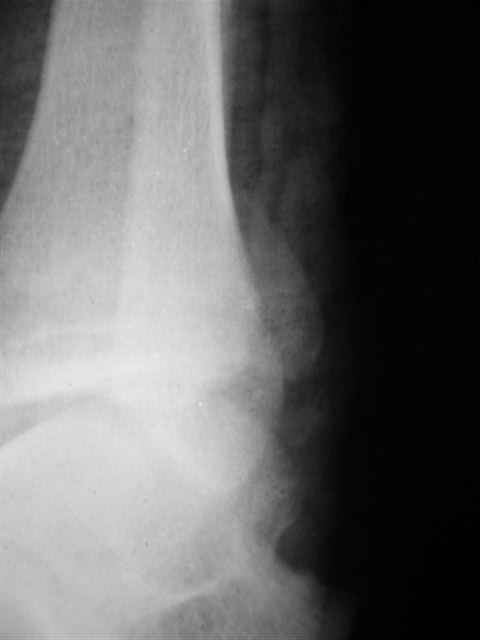

> Если Вас не затруднит, пришлите, пожалуйста, рентгенограммы. Я

> интересуюсь тактикой лечения повреждений голеностопного сустава.

Ничего сверхъестественного, но если есть интерес, то в понедельник пересниму Рг-граммы и отправлю.

Я предупреждал, что ничего сверхъестественного. Каюсь, что одна из спиц прошла несколько дальше, чем нужно было, но главное - перелом стабилизирован и больной работает суставом в полном объёме, несмотря на представленную раннее травму коленного сустава.